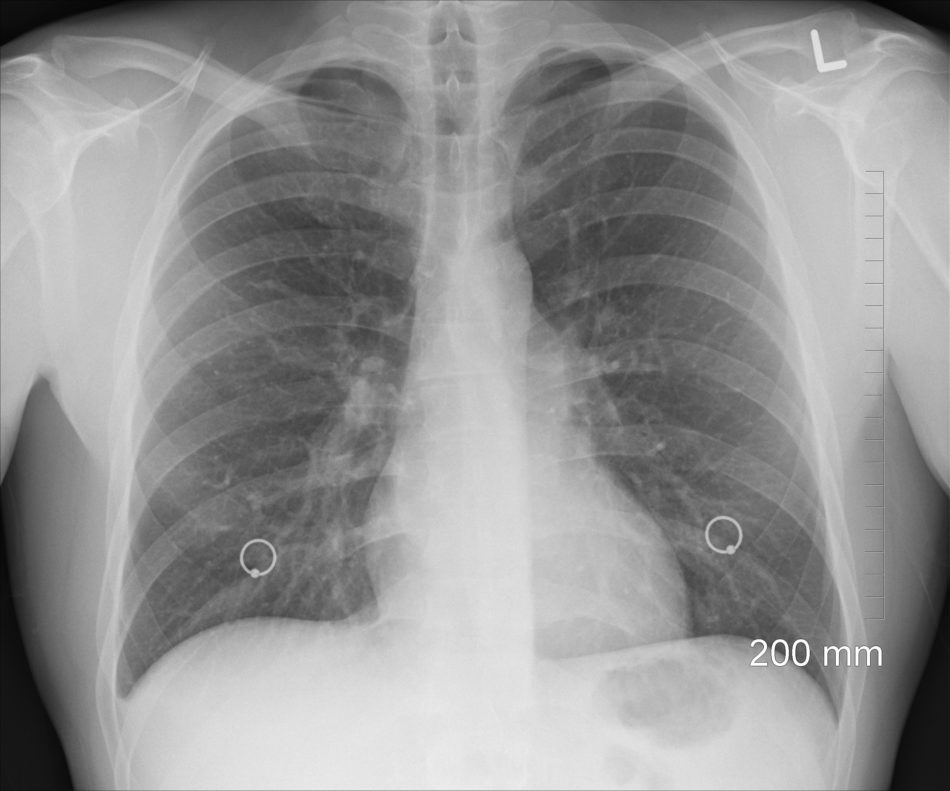

In caso di polmonite, si assiste ad un accumulo di catarro, essudato e pus nei polmoni, che tendono a solidificarsi impedendo il passaggio dell’aria. Generalmente, la polmonite è causata da infezioni di natura batterica, virale o, più raramente, fungina. Anche l’inalazione di liquidi o sostanze chimiche, così come l’aspirazione nell’albero.. Senti “solo” male al polpaccio mentre corri. Senti male a correre, ma a camminare avverti solo un fastidio o addirittura niente. In questo caso è evidente che non si tratta di un problema.

Sintomi del cancro polmonare. Ci sono molti sintomi, oltre alla tosse persistente, associati al cancro del polmone. Alcuni di questi sintomi includono: dolore al petto. tosse con sangue. mancanza di respiro. respiro affannoso o raucedine della voce. problemi di deglutizione. perdita di appetito.. Con il termine polmonite si indica lo stato di infiammazione del tessuto di uno o di entrambi i polmoni. È comunemente causata da un’ infezione batterica ma può essere provocata anche da una infezione virale, fungina o dall’aspirazione di un corpo estraneo. Al termine dei bronchi, “tubi” che trasportano fino ai polmoni l’aria introdotta.